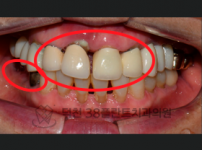

치료전후